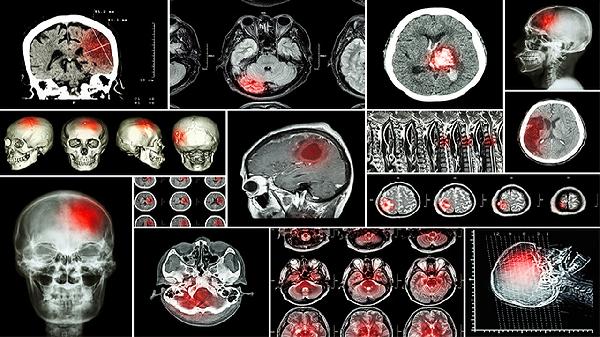

CT检查显示水肿区呈低密度影,MRI的T2加权像可见高信号改变。扩散加权成像有助于区分血管源性与细胞毒性脑水肿,前者表现为表观扩散系数值升高。